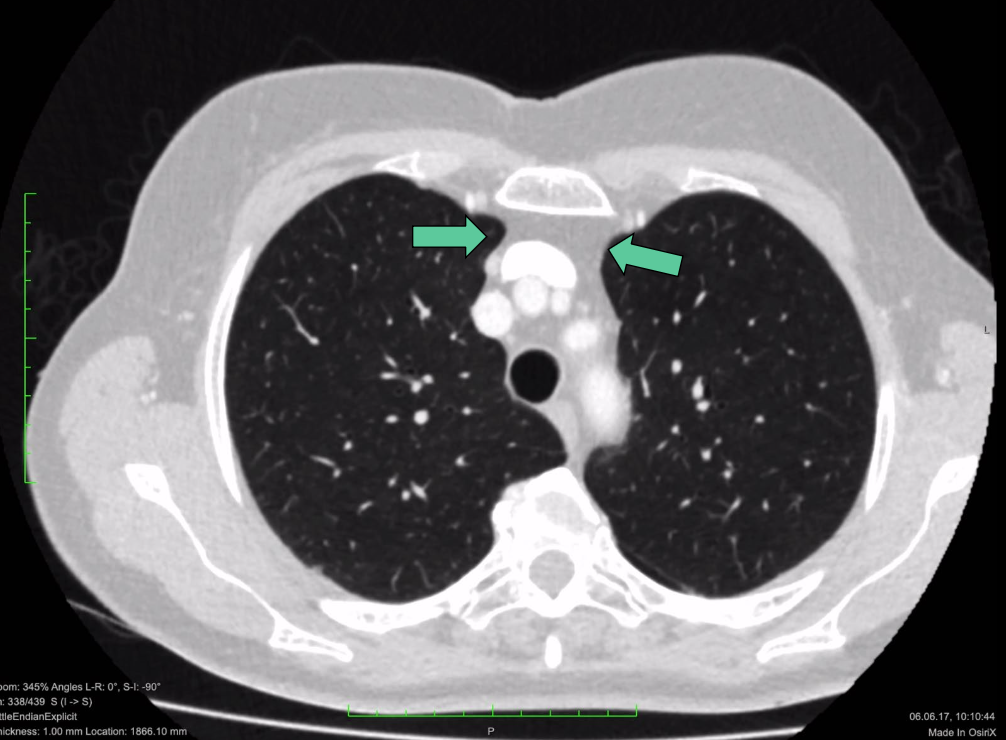

que sont les flèches vertes ?

l’espace rétrosternal